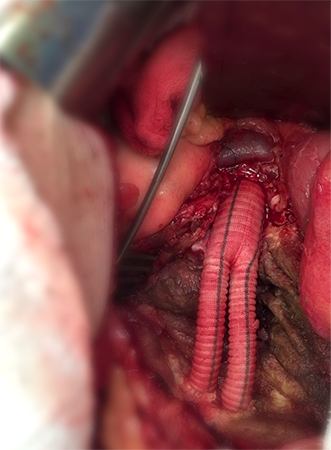

Revascularizações Periféricas

A falta de circulação para os diversos órgãos e membros pode ocorrer de maneira súbita ou gradual. As causas são as mais diversas, entre elas, trombose, aterosclerose, traumatismos, aneurismas, doenças inflamatórias, etc. Em alguns destes casos, a diminuição do fluxo sanguíneo determina um grave comprometimento à vitalidade do membro ou mesmo do órgão. Após detalhada avaliação do caso pelo cirurgião vascular, este pode indicar um procedimento de revascularização.

Através de pontes com material sintético ou biológico (safenas) é possível reestabelecer a circulação aos segmentos mais comprometidos, impedindo a perda do membro ou do órgão. Atualmente também é possível realizar estes procedimentos de forma minimamente invasiva através da cirurgia endovascular.